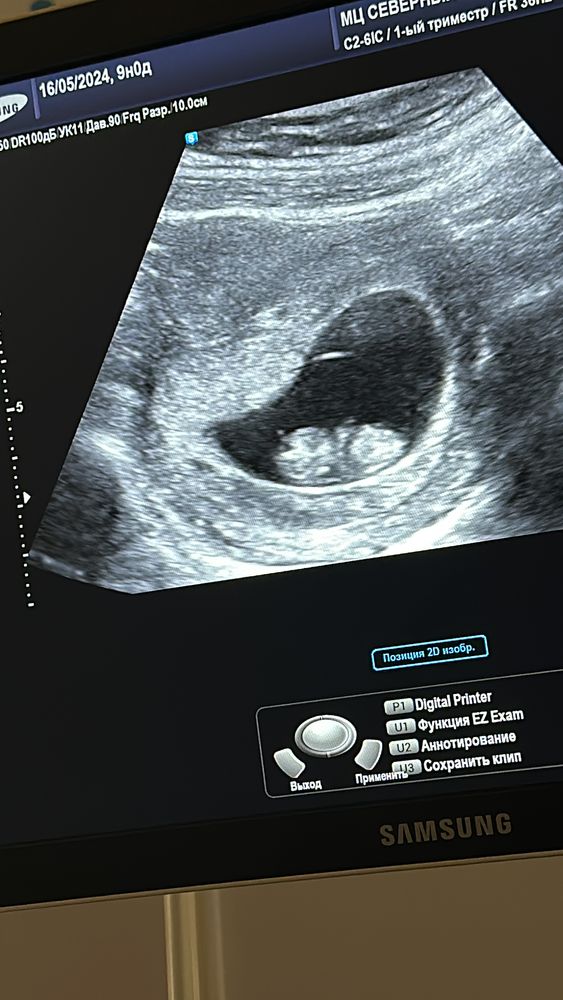

Фоточка осталась только с 9недельки) А сейчас там уже микро человек размером с авокадо..